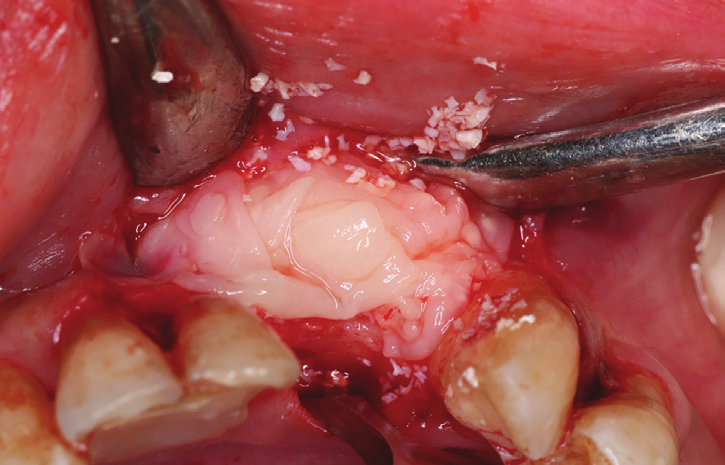

Figure 14: Combination of bovine bone and PRF (Sticky bone).

Figure 15: L-PRF membranes formed in specially fabrication kit.

Figure 27: First layer of L-PRF covering the bovine bone associated PRF complex (sticky bone).

Figure 28: Second layer of L-PRFcovering the cross-linked collagen membrane covering the first complex.

A 33 years-old male patient was visiting our clinic to replace missing teeth no 7 and 8. He was medically fit and mentioned that his teeth were lost due to car accident few years back. Intraoral examination shows absence of space for implant placement and restoration, orthodontic treatment was conducted for 18 sessions followed by surgical implant placement after stabilization of the occlusion. Following the restoration of the space, the amount of horizontal bone loss was evident both clinically and on CAT examinations (Fig.10, 11). A linear incision with mucoperiosteal flap elevation were conducted, the amount of horizontal bone loss was advanced (Fig. 12), which was an indication for autologous bone graft, patient refused to undergo an invasive surgery so PRF associated bovine bone was planned in the area. Blood withdrawal and centrifugation were done with preparation of both L-PRF membranes and sticky bone (bovine bone associated PRF) (Fig.13, 14,15). The combination was placed on the host bone deficiency and covered by a first layer of L-PRF membranes in order to stabilize the graft and insure hemostasis, the second layer of L-PRF membranes covered the cross linked collagen membrane placed in the same area and covering the first entity (Fig.16).

A 38 years-old female patient came to our clinic with swelling upper anterior area, she was medically fit with no health problems. The patient underwent an orthodontic treatment for 2 years and was about to remove it and place retainer. Intraoral examination showed swelling apical area of tooth no 7. The periapical x-ray and CAT view revealed a lateral perforation on the same mentioned tooth with a well circumscribed radiolucency in apical area (Fig.20, 21). Pain on percussion and slight mobility were noted. A surgical enucleation and extraction of tooth no 7 were conducted (Fig.22, 23, 24). 3 months postoperative CAT view shows an advanced horizontal bone loss with no recurrence of lesion in the area (Fig. 26), clinically after reflection of mucoperiosteal flap, the situation confirmed the CAT image (Fig.25) , the case was planned for PRF -associated bovine bone technique replacing the aggressive autologous bone graft procedure. After collection of PRF from patient blood culture, a first layer of L-PRF covering the bovine bone associated PRF complex (sticky bone) was done (Fig.27). The second layer of L-PRF came to cover the cross-linked collagen membrane (Fig. 28).